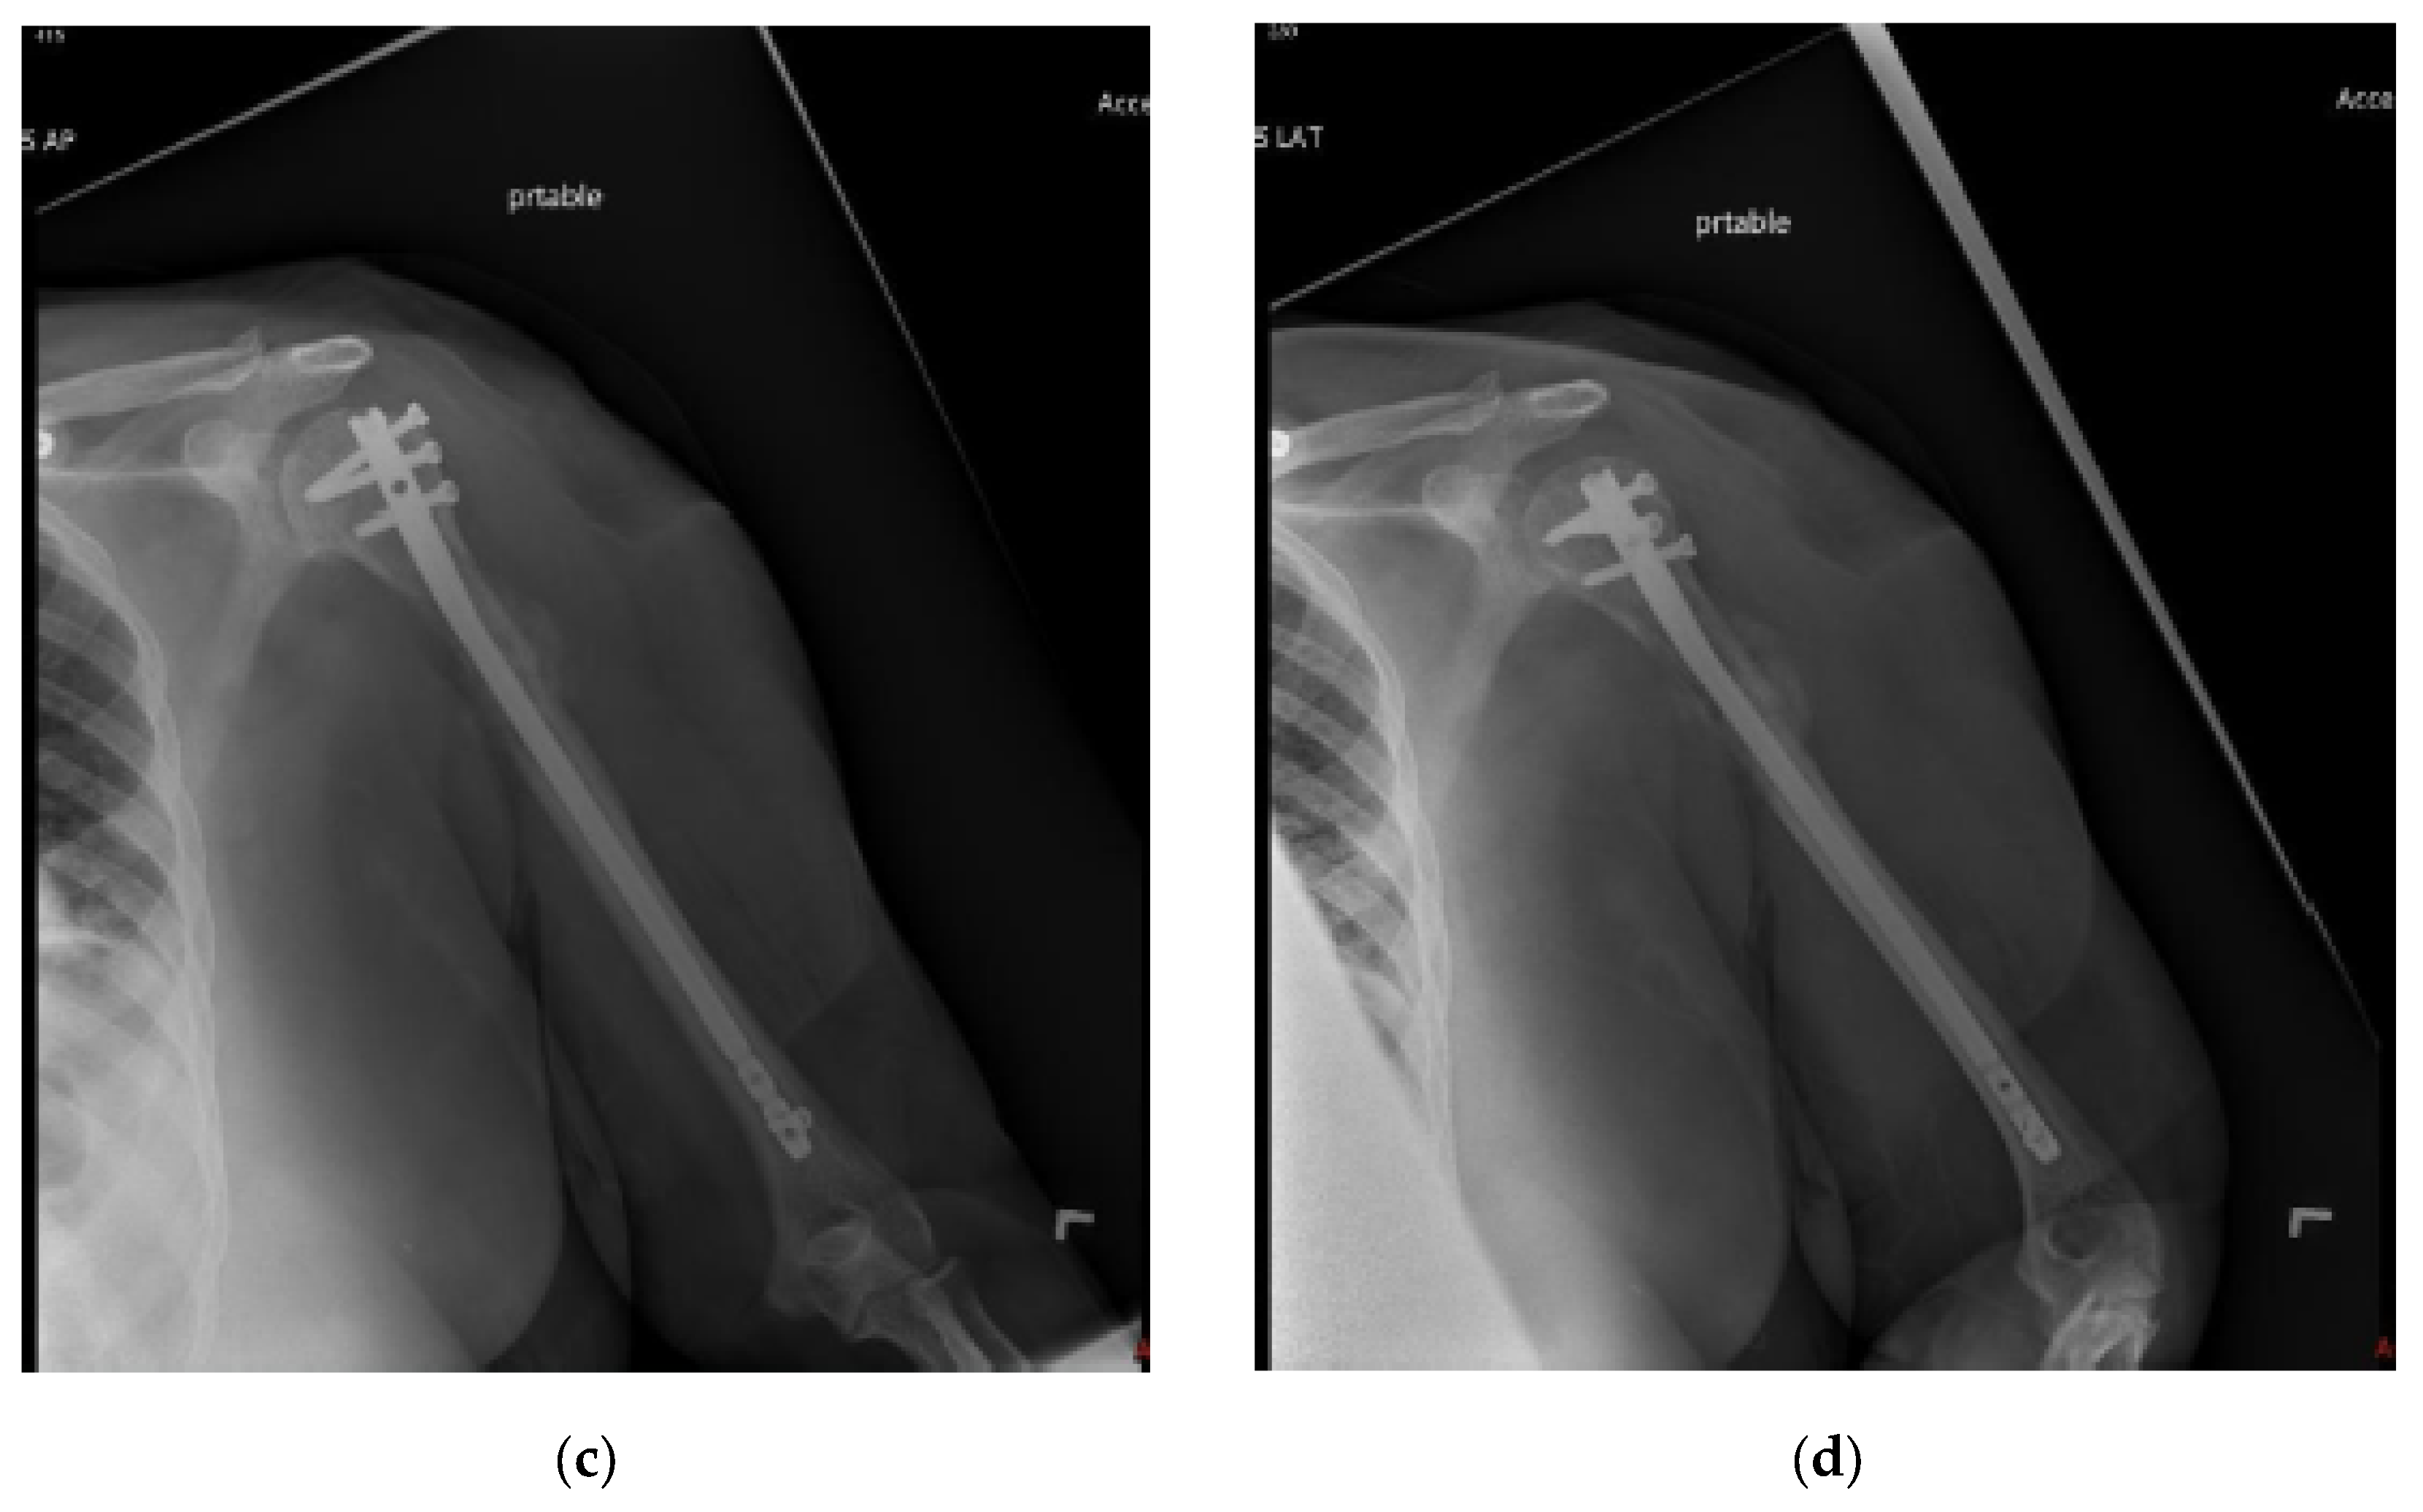

Figure 2.

(a) AP and (b) lateral right humerus radiographs of a 67-year-old male with a mixed lytic sclerotic lesion in the proximal meta-diaphyseal region, with a pathologic fracture from a newly diagnosed metastatic prostate cancer. This was treated by a bone biopsy, followed by a cemented IMN with two proximal inter-locking screws and no distal screw, as shown in the (c) AP and (d) lateral humerus radiographs. Cement was used for augmentation, due to poor proximal humerus bone quality, to support the nail and the inter-locking screws.